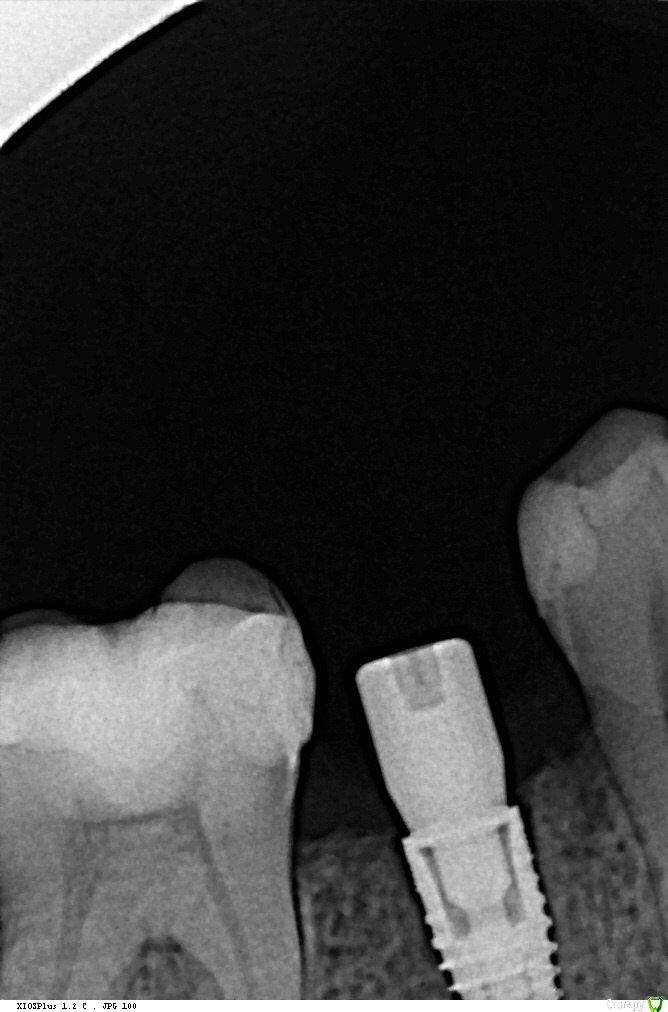

Кариес+ Опубликовано 26 июля, 2016 Поделиться Опубликовано 26 июля, 2016 Добрый день уважаемые коллеги. В область отсутствующего зуба 45 одномоментно после удаления был установлен имплантат нобель 3.5 с торком 35. Первый снимок сразу после установки, вторые через два месяца спустя Ссылка на комментарий

Кариес+ Опубликовано 26 июля, 2016 Автор Поделиться Опубликовано 26 июля, 2016 Смущает щель между импл и костью . Фиброинтеграция или незрелая не рентгеноконтрасная кость? Ссылка на комментарий

TIGER Опубликовано 26 июля, 2016 Поделиться Опубликовано 26 июля, 2016 Такое ощущение,что не дозаглубили........а просто положили в лунку.Надо было заглубить там кости полно,это важный момент для одномоментной 2 Ссылка на комментарий

Nazim_NV86 Опубликовано 26 июля, 2016 Поделиться Опубликовано 26 июля, 2016 Такое ощущение,что не дозаглубили........а просто положили в лунку.Надо было заглубить там кости полно,это важный момент для одномоментнойНе всегда удаётся заглубить. Дать торк главное, минимум 50. Ссылка на комментарий

Доктор Хаус Опубликовано 4 августа, 2016 Поделиться Опубликовано 4 августа, 2016 Ой тест делать с анестезией ? Вот если случай без фдм а с заглушкой ? Небольшую инфильтрацию дать чтобы заглушку убрать и поставить имплантовод и дать нагрузку в 30-35н/см ?Даже с проводниковой анестезией будет больно, если произошла фиброинтеграция . А она происходит от того костное ложе перегрето или косное ложе не конгруэнтно самому имплантату . Для себя я четко усвоил что при одномоментный имплантации около 4 х мм имплантата должно быть в кости . По прицельным снимкам у меня сложилось впечатление что имплантат закручен в лунку. И костного ложа , здесь как такового нету . Вполне вероятно, что здесь произошла фибро интеграция ( неприжился) и поэтому на прицельном снимке вокруг имплантата определяется зона пониженной плотности. Ссылка на комментарий

Доктор Добрых Дел Опубликовано 6 августа, 2016 Поделиться Опубликовано 6 августа, 2016 Вообще не вижу разницы между 3мя снимками. И на первом и на втором видна "щель". Ссылка на комментарий